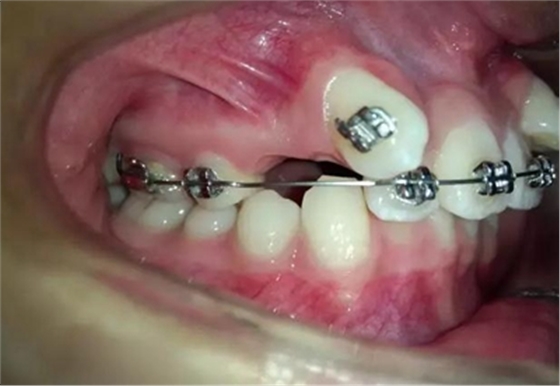

手術(shù)切開,去除上部牙槽骨暴露出來牙尖,可以看到尖牙緊緊壓在側(cè)切牙根尖唇面上。

粘上舌側(cè)扣用結(jié)扎絲附弓結(jié)扎

幾天過后病人向我反應(yīng)側(cè)切牙壓痛松動

我考慮一下應(yīng)該是尖牙牙冠壓迫壓迫側(cè)切牙的根尖部導(dǎo)致的疼痛和松動

考慮到如果能像種植支抗,水平方向或者向唇側(cè)牽引移動,可以有效避免垂直方向牽引力壓迫側(cè)切牙根尖部,所以我和病人溝通了一下,建議采用種植支抗,但是病人不想增加費用。

那好吧還是采用輔弓增加支抗,經(jīng)濟適用,也便與操作,0.8不銹鋼絲彎制,進行熱處理,增加其彈力。

結(jié)扎固定